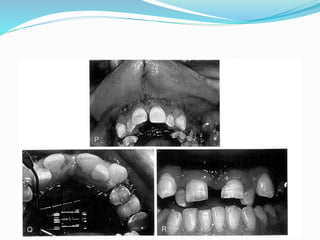

 Ischemic zone

MarginalGingival necrosis

Complications

 Gum retraction

 Osteotomy site